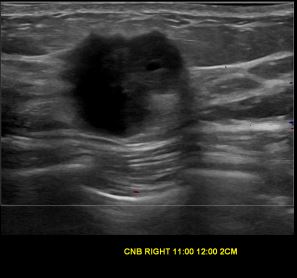

상기환자는 우측 유방 만져지는 멍우리로 내원하신 20대중반 여성분으로 의심스러운 우측혹 조직검사 시행해 유방암으로 진단되었습니다